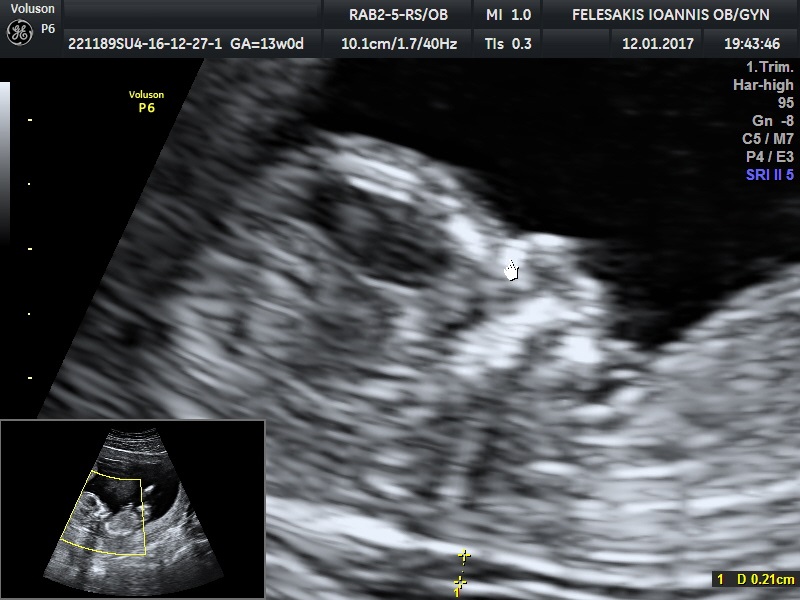

Το υπερηχογράφημα αυτό πραγματοποιείται μεταξύ 11 και 13+6 εβδομάδας συνήθως διακοιλιακά. Ελέγχεται η ανάπτυξη του εμβρύου, η ανατομία του και προσδιορίζεται η πιθανότητα για χρωμοσωμικές ανωμαλίες όπως το Σύνδρομο Down (Τρισωμία 21), σύνδρομο Edwards (Τρισωμία 18), Patau (Τρισωμία 13). Η ηλικία της μητέρας, υπερηχογραφικές μετρήσεις και βιοχημικές παράμετροι συνυπολογίζονται από ένα πρόγραμμα το οποίο παρέχεται στους πιστοποιημένους ιατρούς για τη διενέργεια της αυχενικής διαφάνειας από το Fetal Medicine Foundation. Πρωτοπορος της μεθόδου αυτής είναι ο καθηγητής Κύπρος Νικολαΐδης ιδρυτής του Fetal Medicine Foundation ( King's College Hospital- Λονδίνο - Ηνωμένο Βασίλειο)